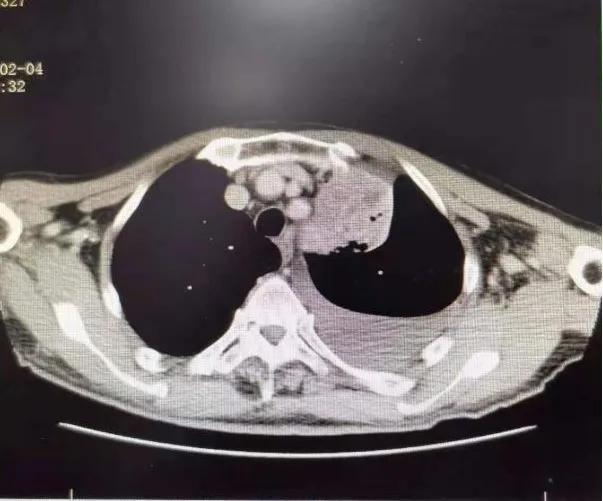

75岁的张爷爷患有慢性阻塞性肺疾病、脑栓塞等多种慢性病,体质较差,PS评分为3分,入院时有咳嗽咯血伴有气短乏力等症状,查胸部CT可见左上肺叶大小约8×4cm大小占位病变,纵隔淋巴结肿大,左侧大量胸腔积液。 气管镜可见左上支气管内新生物阻塞。 病理提示: 鳞状细胞癌。 诊断为: 肺癌(左肺 鳞癌 cT4N2M1a,IVA期)。 确诊后家属考虑患者年老体弱,合并多种疾病,拒绝放化疗,准备放弃治疗。

1个月后张爷爷来院复诊,复查胸部CT提示:左肺上叶肿块缩小到1cm,肺不张明显缓解,胸腔积液减少 。 张爷爷表示近1月来态势明显好转,未再咯血,活动也不像之前那样一动就喘,平时走路吃饭都不影响。入院后PS评分1分,临床疗效评估为PR。 为更好的控制肿瘤,进行了第二次介入治疗。 行支气管动脉及胸廓内动脉造影后显示肿瘤染色明显减少,继续灌注化疗药物后,将肿瘤滋养动脉进行了彻底栓塞。 术后无不适, 顺利完成第二次治疗。